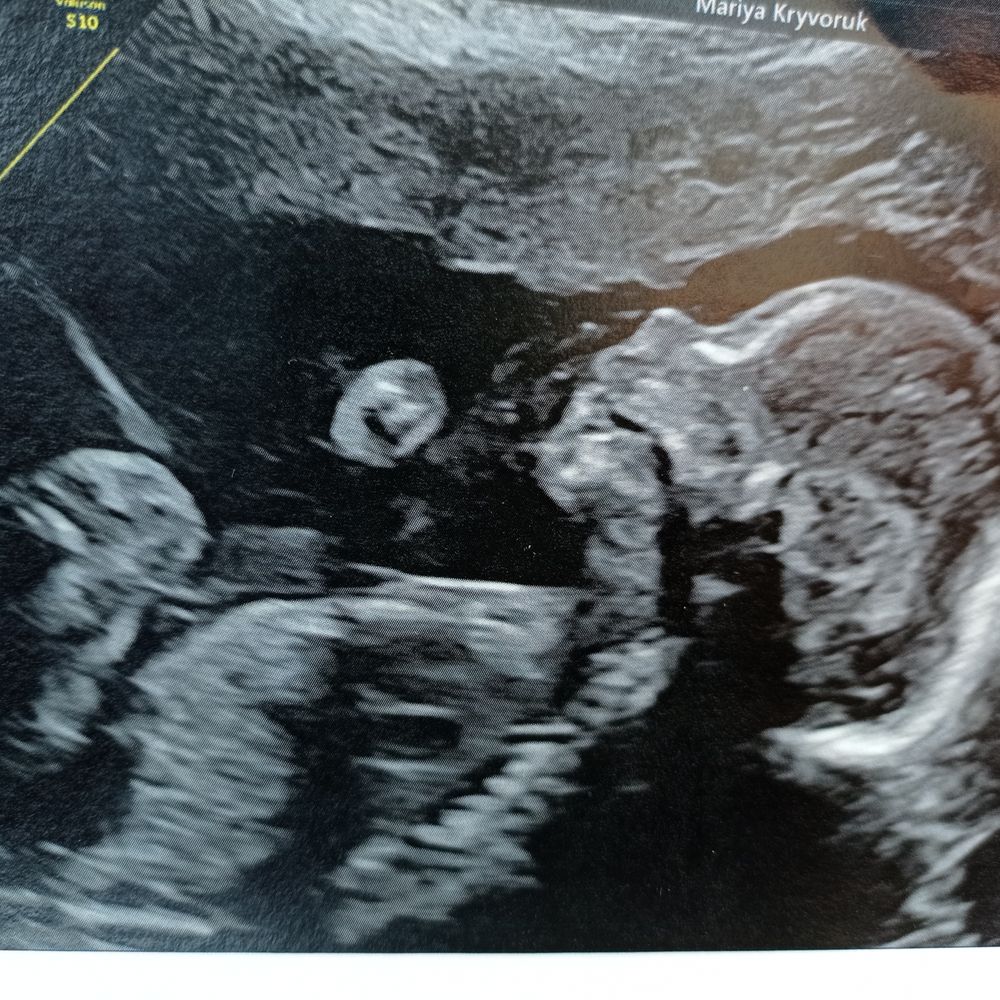

Редко пишу, но сейчас решила, есть повод) В пн прошли экватор - 20 неделек, а сегодня был второй скрининг. Всё отлично у нас с доцей! Такой человечек там уже😍. А, кажется, совсем недавно я писала сюда на первых недельках, вся такая перепуганная и расстроенная из-за нерастущего хгч!